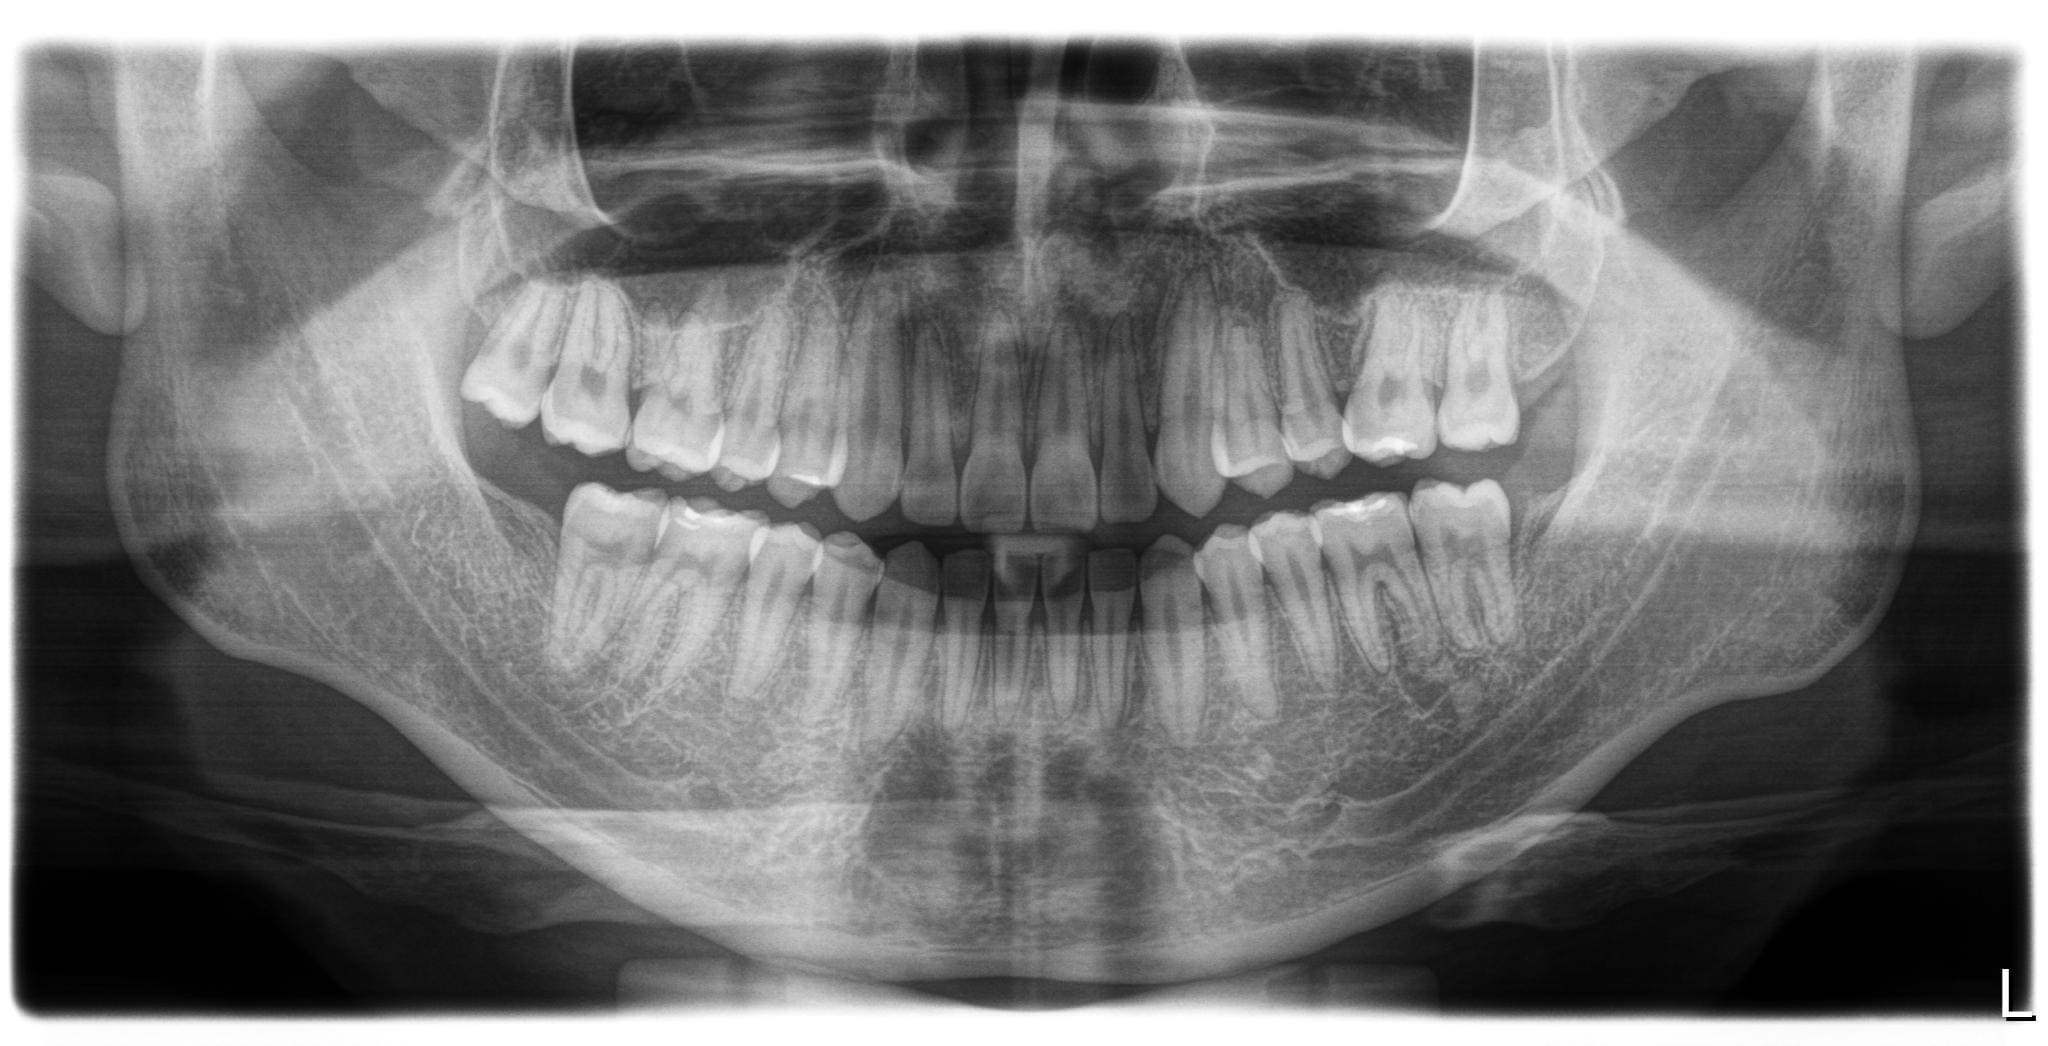

病患在三年前第一次來到森釉診所,當時的主訴是因為覺得自己的牙齒排列不夠整齊,特別是後方缺牙的地方,旁邊的牙齒已經開始往缺牙處倒塌,加上下巴有些往前突出的情況,希望我們能夠幫他進行完整的矯正評估和治療規劃。

經過仔細檢查後,我們發現病患的口腔狀況存在幾個需要處理的問題。首先是左上方的臼齒因為嚴重蛀牙只剩下牙根,導致兩側的牙齒失去支撐而逐漸傾倒,進而影響了整體的牙齒排列。另外,下排牙齒有錯咬的狀況,造成下巴看起來往前凸。除此之外,由於病患本身的牙齒比例偏短,笑的時候牙齦露出的面積相對比較多,影響了整體的美觀性。

針對這些問題,我們擬定了完整的治療方案。首先,利用矯正的方式,將後方的第二大臼齒和智齒慢慢往前移動,填補缺牙的空間,同時調整上下排牙齒的咬合關係,讓錯咬的情況回復到正常的咬合狀態。當矯正治療完成後,病患的狀況其實已經改善了許多。